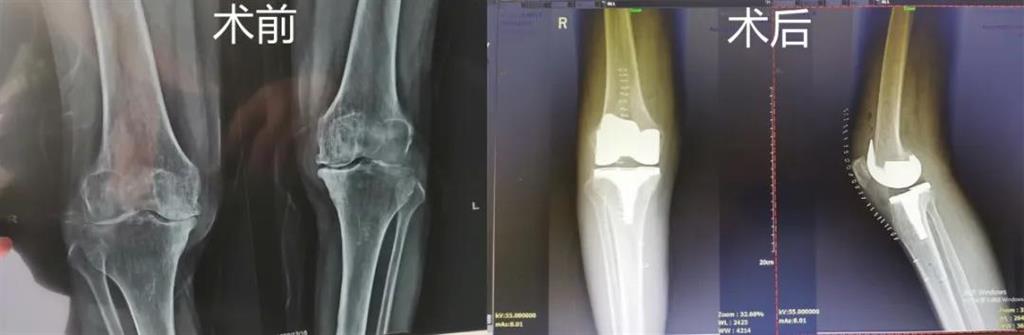

最近,和平國際醫(yī)院骨科中心開展了一項(xiàng)新業(yè)務(wù)——計(jì)算機(jī)導(dǎo)航膝關(guān)節(jié)置換術(shù),而年邁78歲的李奶奶則幸運(yùn)地成為該手術(shù)的首個受益者。這也是溫州地區(qū)率先將骨科傳統(tǒng)手術(shù)與計(jì)算機(jī)導(dǎo)航系統(tǒng)相結(jié)合應(yīng)用的成功案例,也是和平國際醫(yī)院骨科中心在膝關(guān)節(jié)置換術(shù)方面所取得的一次重大突破!

李奶奶已經(jīng)被兩側(cè)膝關(guān)節(jié)疼痛困擾了5年左右時間,尤其是右側(cè)膝關(guān)節(jié),近一年來癥狀明顯加重,無法正常生活。經(jīng)過多方打聽,一家人來到和平國際醫(yī)院。

和平國際醫(yī)院副院長、骨科中心主任劉丹在診斷后發(fā)現(xiàn),老人雙側(cè)膝關(guān)節(jié)患有骨性關(guān)節(jié)炎,右側(cè)膝關(guān)節(jié)較為嚴(yán)重,而且關(guān)節(jié)磨損嚴(yán)重,關(guān)節(jié)間隙基本消失。

經(jīng)過進(jìn)一步檢查后,劉丹帶領(lǐng)團(tuán)隊(duì)在計(jì)算機(jī)導(dǎo)航系統(tǒng)的輔助下,為老人實(shí)施了右側(cè)全膝關(guān)節(jié)置換手術(shù)。術(shù)中出血明顯減少,術(shù)后疼痛腫脹等反應(yīng)輕微,畸形矯正力線恢復(fù)理想,而且功能恢復(fù)快速,術(shù)后四天就可以下地行走。

據(jù)劉丹主任介紹,計(jì)算機(jī)導(dǎo)航膝關(guān)節(jié)置換術(shù)可以避免打開股骨髓腔,從而明顯減小手術(shù)創(chuàng)傷,減少術(shù)中出血,能夠更精準(zhǔn)地從三維角度調(diào)整手術(shù)截骨方向,恢復(fù)肢體對線,并能進(jìn)行精確的軟組織平衡,從而使患者獲得良好的術(shù)后功能恢復(fù)。